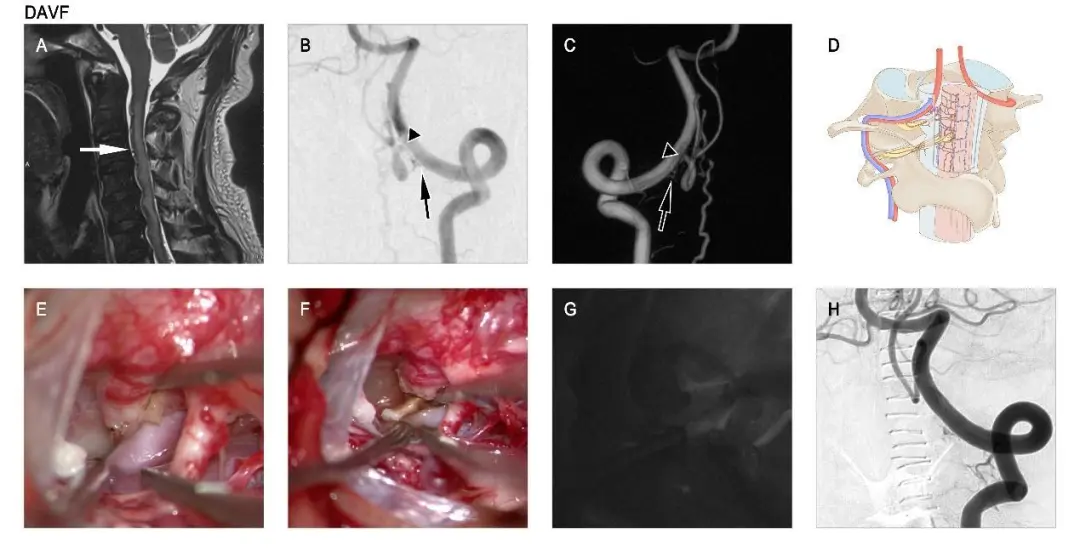

A male with CCJ DAVF patient started with venous hypertensive myelopathy and underwent microsurgery. T2-weighted sagittal MRI image (A) shows cervical medullary high signal and flow-vessel shadows (white arrows in A). Preoperative angiography of the left vertebral artery (B and C). This AVF is supplied by the dural branch of the left C-1 vertebral artery (black arrow in B and C), which drains into the intradural vein (black triangle in B and C). Schematic diagram of the AVF (D) vascular configuration. Intraoperative image showing the AVF and draining vein (E). Intraoperative images and ICG fluorescence angiography show the AVF (F and G) severed. Left vertebral artery angiography at 4 days postoperatively (H).

Overall the most common location of onset in CCJ AVF is at the C-1 level, whereas EDAVF and PAVF in more commonly develop at the C-2 level. In this study, male patients predominated, with a total of 138 (83.6%) CCJ AVFs being male. DAVF mainly started as venous hypertensive myelopathy, while other types of CCJ AVFs often started as subarachnoid hemorrhage. In the treatment of CCJ AVF, the preferred therapeutic strategy is microsurgery, whereas interventional embolization can be used for the treatment of CCJ AVF in specific vascular constructs or to embolize part of the vascular malformation where surgical exposure is difficult before microsurgery.